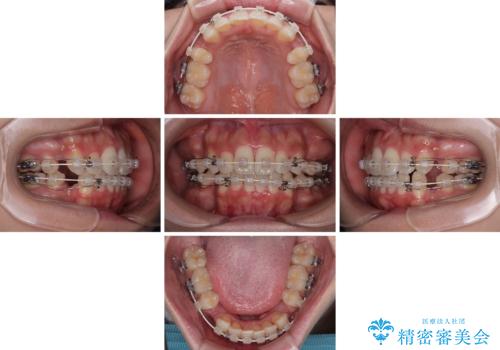

横顔の印象を改善したい ワイヤー装置での抜歯矯正

- 口元の突出感と口の閉じにくさを気にして来院された患者様です。

上下左右第一小臼歯4本を抜歯し、ワイヤー装置にて口元を引っ込めるよう矯正治療を行うこととしました。

口元の突出感が改善されてことで、下唇に引っかかっていた上顎前歯も気にならなくなりました。